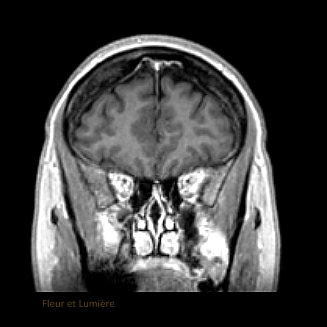

Quand en regardant ton IRM cérébrale tu te rends compte que dans ta tête y'a des têtes!

Au centre le nez

Sur les côtés, deux yeux

Un grand front

Des grands cheveux

En bas une bouche.

Avec des expressions différentes